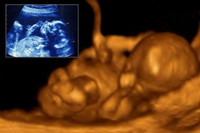

懷孕六個(gè)月男胎兒有多大,懷孕六個(gè)月按孕周期來計(jì)算的話,即是懷孕21周-懷孕24周,此時(shí)的胎兒體重開始大幅度的增加,看上去已經(jīng)很象小寶寶的樣子了,不過皮膚依然是皺的,紅紅的,樣子像閱讀全文>>

六個(gè)月的胎兒長成什么樣子,他在四肢,五官,胎長方面都增長了多少呢?還有懷孕進(jìn)入六個(gè)月時(shí),孕婦會(huì)里而感覺便秘,腰酸背痛的情況,其實(shí)那是你沒有遵守此階段的注意事項(xiàng)。如果你還不...閱讀全文>>

懷孕六個(gè)月孕媽已進(jìn)入懷孕中期,這個(gè)時(shí)候最讓孕媽激動(dòng)和不安的事情,應(yīng)該算是胎兒的胎動(dòng)了,很多孕媽有些搞不清楚懷孕六個(gè)月胎動(dòng)是什么樣子的,怎樣的才算是正常的狀況?其實(shí)...閱讀全文>>